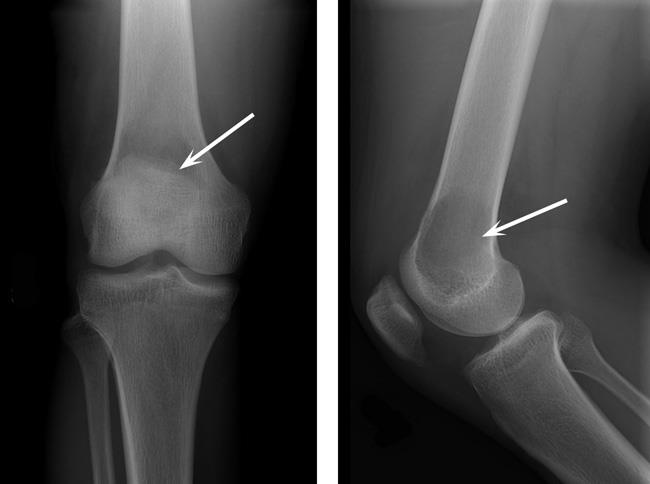

संग्रह 2021: जाइंट सेल ट्यूमर एक्स रे

यहां आपको वह मिलेगा जिसकी आपको तलाश थी - जाइंट सेल ट्यूमर एक्स रे

X Ray Multiple Part Of Child S Body Multiple Disease Stroke Brain Tumor Rheumatoid Arthritis Sinusitis Gouty Arthritis Etc Skull Chest Lung Heart Spine Arm Hand